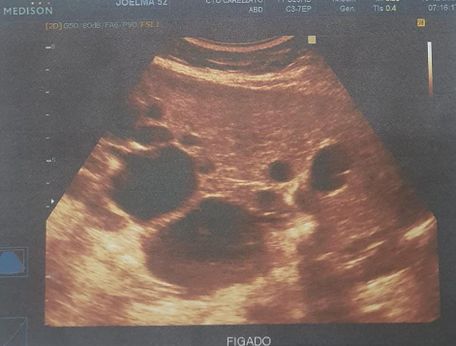

Foi realizado exame de imagem (21/10/2024), ultrassonografia abdominal com os seguintes achados (figura 1.1, 1.2, 2 e 3) Exames laboratoriais (21/10/2024): Acido úrico 2 mg/dl, Bilirrubina total 0,37 mg/dl, Bilirrubina direta 0,18 mg/dl, Bilirrubina indireta 0,19 mg/dl, TGP 21 u/l, TGO 16 U/L, Uréia 34 mg/dl, Creatinina 0,51 mg/dl, Sorologia para hepatite B, C não reagente.

Figura 1.1

Figura 1.1 e 1.2: identificando fígado de contornos irregulares, parênquima heterogêneo, ecogenicidade aumentada, trama vascular diminuída e volume aumentado, múltiplos cistos no parênquima hepático, o maior no lobo esquerdo medindo 8.9 cm x 7.0 cm.